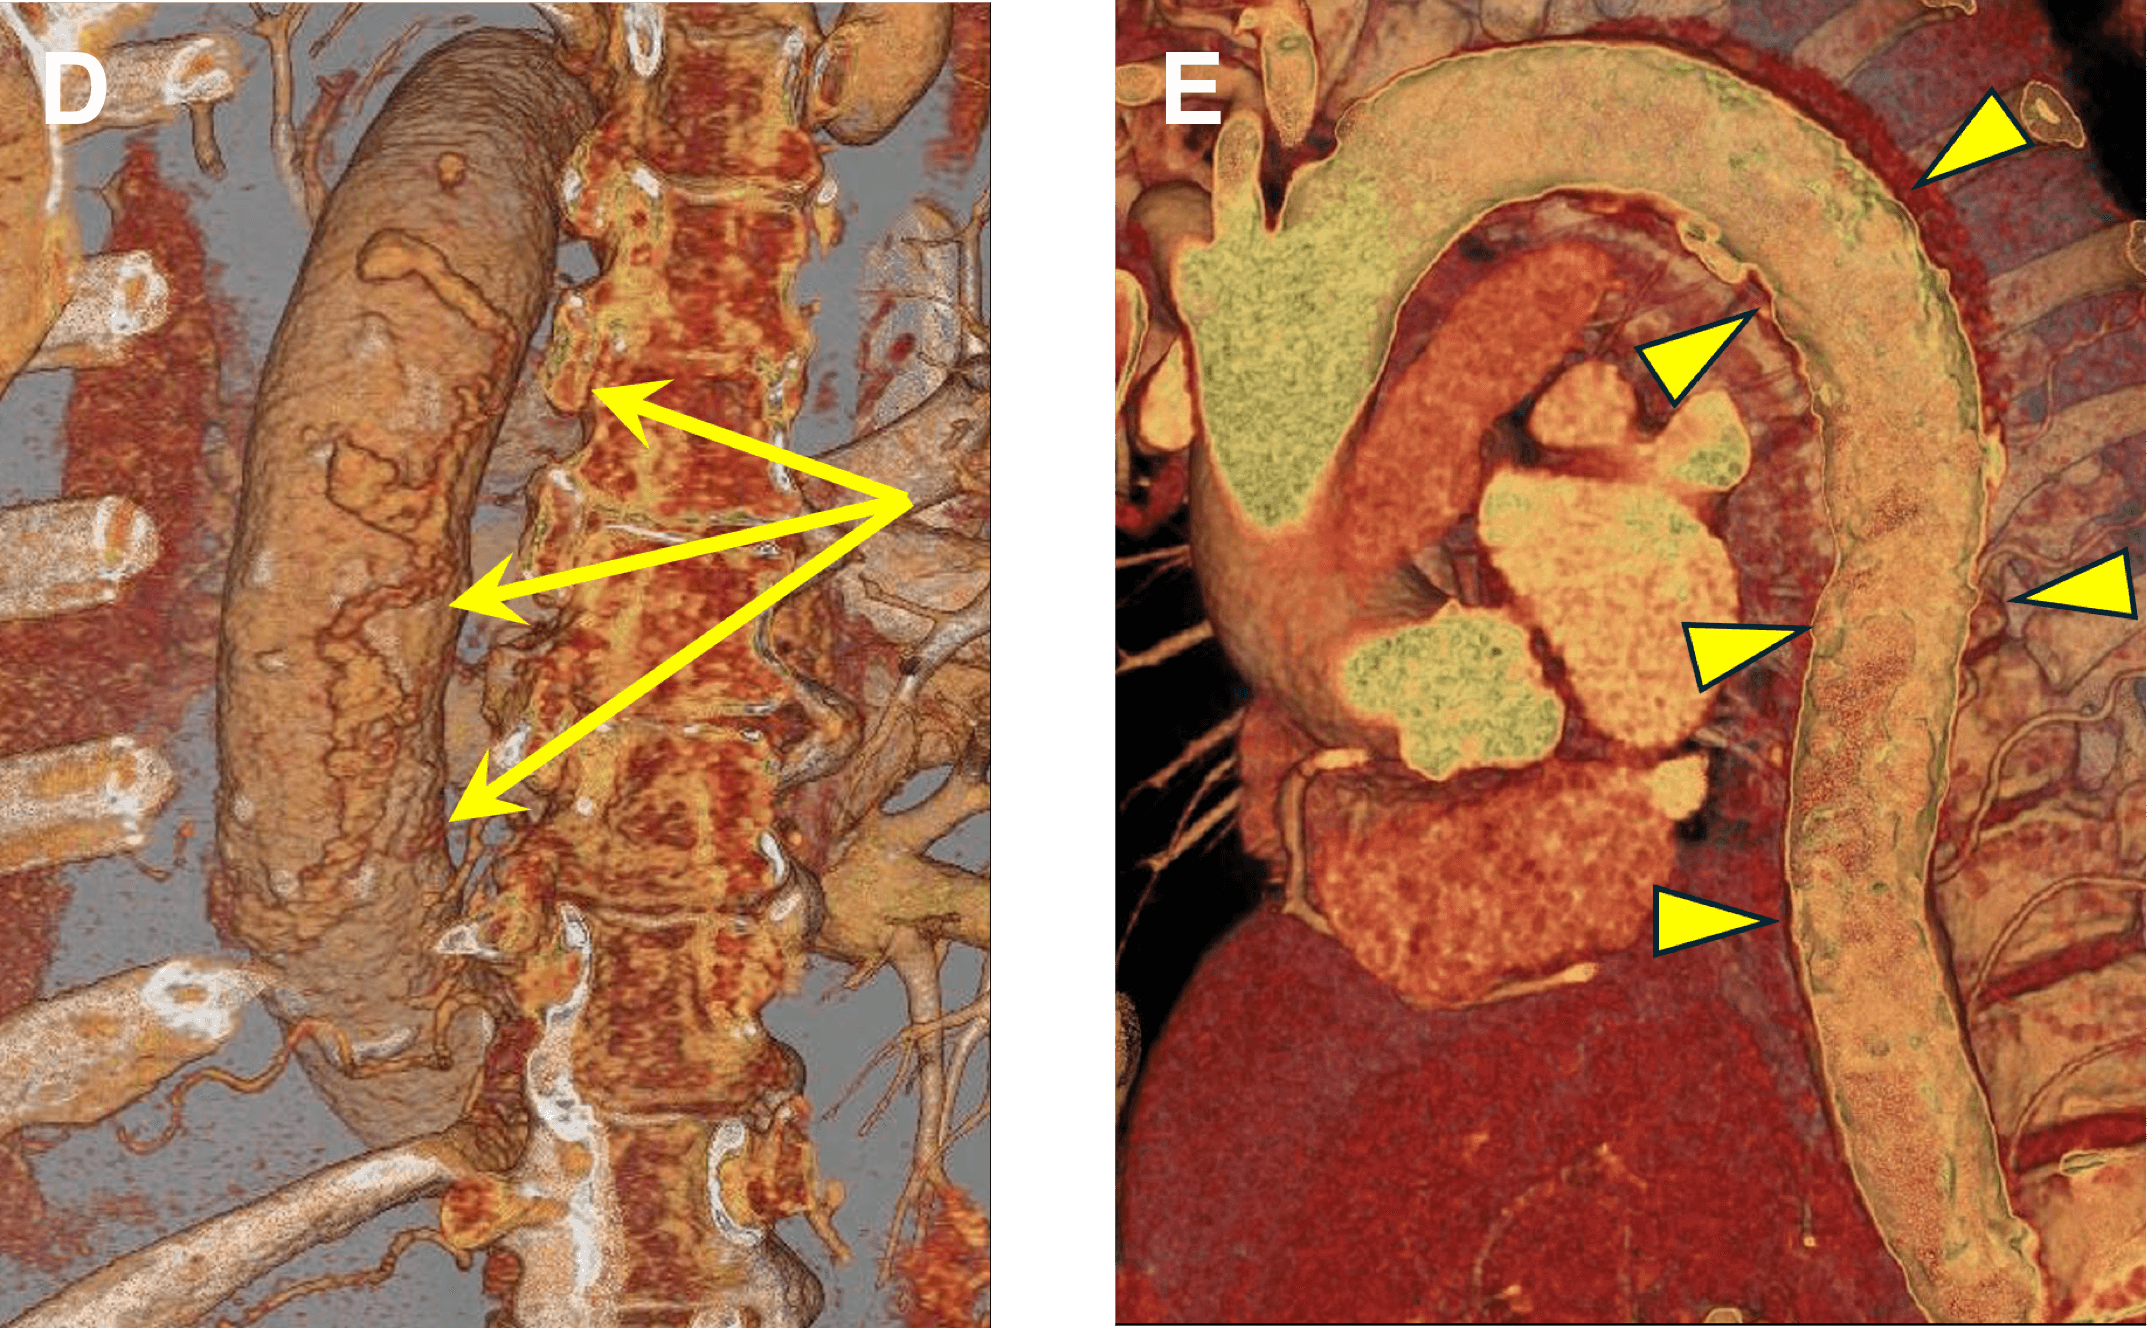

Figure B. Non-contrast series shows high density within the wall of the aorta, consistent with intramural hematoma (IMH, arrow).

Figure C. CTA images shows an adjacent ulcer-like projection (arrow, ULP).

Figure C. Volume-Rendered image viewed from posterior shows multiple outpouchings of contrast extending into and beyond the expected aortic wall (arrows).

Figure D. Blood pool inversion (endoluminal) VR image shows shaggy, irregular endoluminal surface (arrowheads).

IMH occurs from penetrating atherosclerotic ulcer (PAU) that extends across the internal elastic lamina into the media and/or adventitia. Ruprture of the vaso vasorum occurs, and blood collects in the aortic wall = IMH (arrow in B) . Extension though the adventitial structures can result in pseudoaneurysm or rupture (arrow in C).